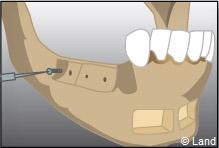

Apposition et stabilisation du greffon.

Après 6 mois de cicatrisation, il est possible de poser les implants qui recevront dans un deuxième temps les couronnes.

Apposition et stabilisation du greffon.